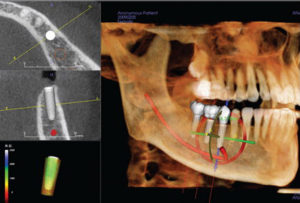

Precizno planiranje podrazumeva detaljnu dijagnostiku, 3D snimke i individualni pristup kako bi implant bio stabilan, bezbedan i dugotrajan

U radu koristimo najsavremeniju tehnologiju, uključujući 3D skener, digitalno snimanje zuba, laserski potpomognuto lečenje i 3D planiranje budućih zuba, što omogućava preciznije dijagnoze, bezbolnije tretmane i vrhunske estetske rezultate.